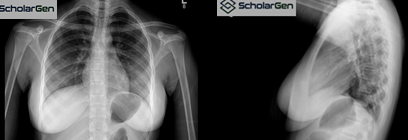

Chest X-ray was unremarkable, showing no

signs of active pulmonary TB.

Chest imaging is essential to rule out concomitant

pulmonary TB.

Explanation: Even in cases where

cervical TB is suspected, it is critical to rule out pulmonary involvement,

which determines infection control precautions and guides treatment. Chest

radiography is fast, accessible, and highly informative.

5. The

patient has a normal chest x-ray.

A) TRUE

B) FALSE

Explanation: The chest X-ray

revealed no active disease, pleural effusion, or lung involvement. However, it

is important to note that normal chest X-ray findings do not exclude TB

lymphadenitis, as up to 50% of these cases occur without pulmonary disease.